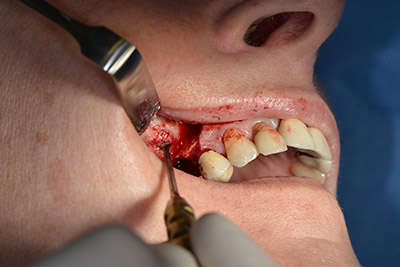

The classic incision (crestal, buccal relief) and the preparation of the mucoperiosteal flap enabled a good overview.

Sky implants (bredent) were used this case. The surgical protocol of these, specify pilot drilling at about 1200 rpm (Fig. 9).

The following holes were drilled at a reduced speed of 300 rpm. The Implantmed demonstrated its true capability at this stage. The surgical protocol can be preset – the various positions can be selected simply by pressing the “P” position of the foot control (Fig. 10 to 11).

Inclined drilling

Image 10: Inclined drilling to dorso-cranial at 300 rpm.